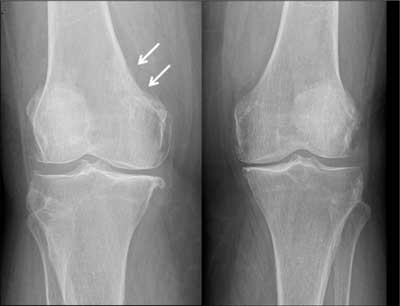

Figure 1

AP views of both knee joints: Obvious bilateral gonarthrosis. The erosive lesion in the medial cortex of distal metaphysis of right femur and associated discrete subcortical sclerosis (arrows) can be easily missed. Compare with the smoothly outlined medial cortex of left femur.